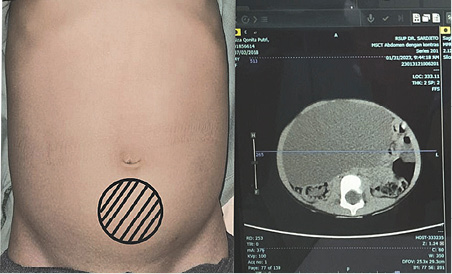

A 4-year-old girl reported having a abdominal distension for two months, there was no history of abdominal pain, vomiting, fever, and no disorders of respiratory or urinary system. Her growth and development were normal and no family history of similar illness; the anamnesis provided the diagnosis. Abdomen was distended with a 15 cm by 15 cm mass with dull percussion, non-tender smooth surface, well-defined border, movable from side to side in the top border, initially around the pelvic area and later to periumbilical area 1 cm under umbilical (Figure 1). Her blood profile, coagulation profile, albumin level, electrolytes, renal and liver functions tests were normal and no hepatitis B surface antigen was found. CT abdomen with intravenous contrast revealed a large cystic mass lesion (Figure 2) with internal septations, origin from the ovary with extending from the pelvis to the cavum abdomen. Other abdominal organs were normal.

Figure 1. Anterior view of the patient’s abdomen